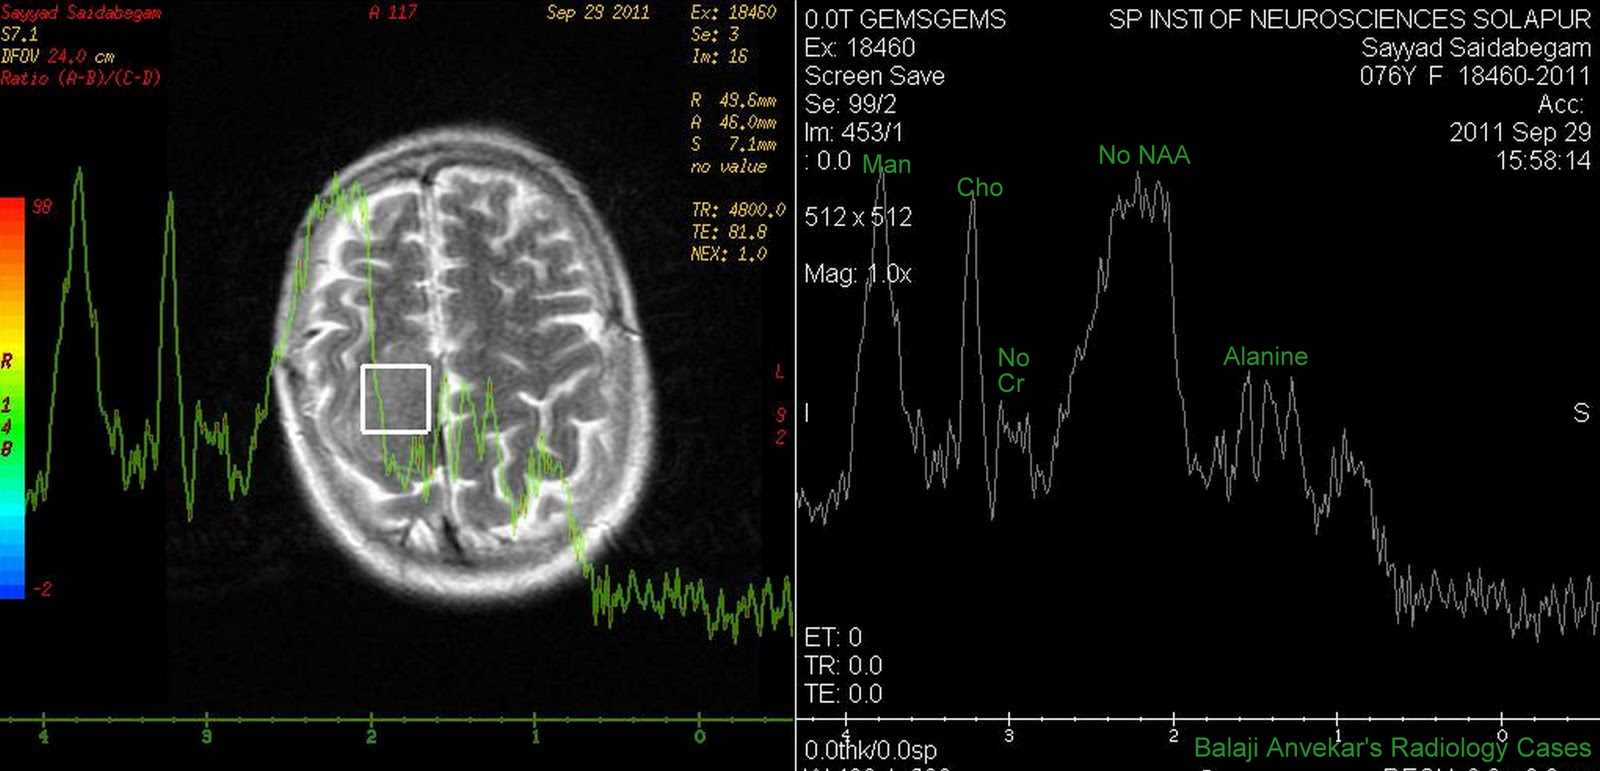

From radiocases.blogspot.com

Dr Balaji Anvekar's Neuroradiology Cases Meningioma MR Spectroscopy Spectroscopy Mri Radiology this work provides an overview of the use of mr spectroscopy in brain tumor imaging, including general imaging principles and technique,. mr spectroscopy is used worldwide as an adjunct to mr imaging in several common neurologic diseases,. this work provides an overview of the use of mr spectroscopy in brain tumor imaging, including general imaging principles and.. Spectroscopy Mri Radiology.